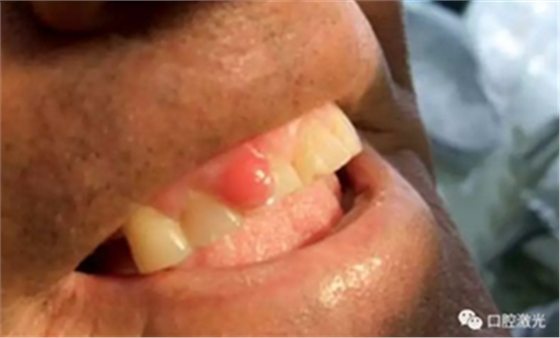

龈瘤指的是任何位于牙龈部的良性纤维瘤病变。龈瘤通常呈粉红色,虽然为良性,但会随牙龈一同生长,有时会因体积过大而包裹一颗或多颗牙齿。目前,龈瘤的具体病因上不可完全清楚,一般采用外科手术切除是被认为是安全的,其中就包含利用口腔激光进行切除。口腔激光拥有许多的波长,都可以用到龈瘤切除等软组织手术中,并且拥有快速凝固和高效灭菌的特点。

本文收集了多位年龄在14至50岁的龈瘤患者,均活检诊断后确认。所有手术均在门诊完成,全部使用半导体口腔激光。其功率设置为:4至6W,连续模式。光纤芯径300微米。所有的患者都在术后1周,4周,6个月以及1年时间复诊,评估激光手术的长期效果。

在治疗前,患者、医生及助手均佩戴正确的防护眼镜,并且对患处进行拍照记录。随后使用2%的利多卡因 1cc进行浸润麻醉。激光器设置完毕后,采取外切的手法,利用镊子将龈瘤拉伸后,从其根部进行外切。手术后无需缝针,并对切除物进行病理学检查。检查结果确认为纤维瘤。整个手术过程通常为4至6分钟。建议患者术后冰敷以减少水肿发生。